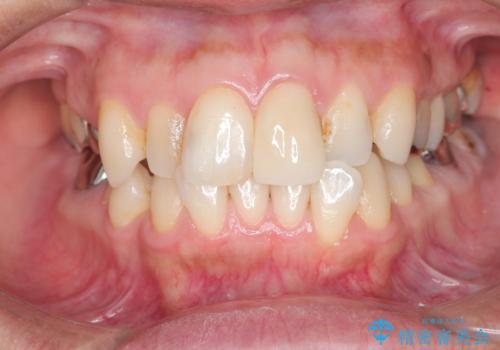

転んで折れた前歯セラミック治療で審美改善

- 自転車で転倒してしまい、前歯を折ってしまい、痛みと見た目の改善を希望され来院されました。

もともと根管治療の為されて歯が折れてしまっているので、根管治療を行い審美的なセラミック治療を行う治療計画としました。

周囲の歯と調和した審美的な仕上がりに満足いただくことができました。